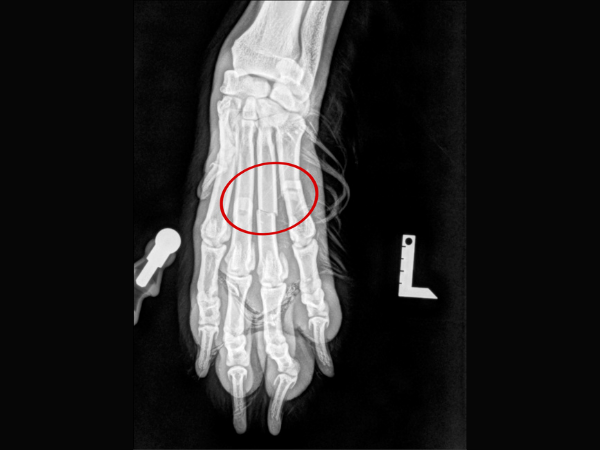

<術前のレントゲン>

第2・3・4指中手骨を骨折しています。

▼術前